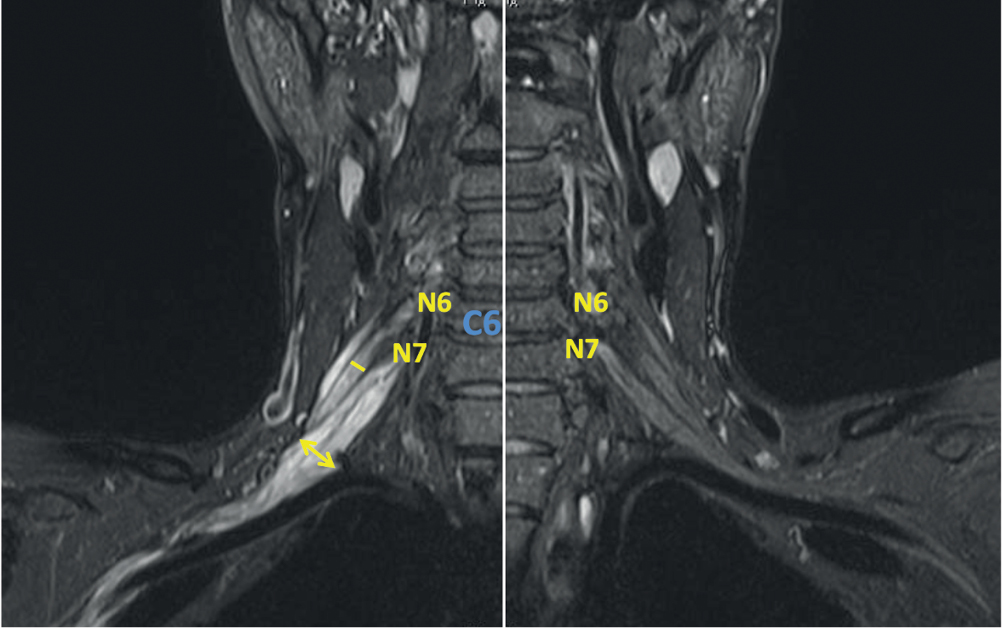

Рис. 5. МРТ ПС пациента с ММН (катамнез 10 лет, исследование выполнено до начала патогенетической терапии). В режиме STIR в коронарной проекции отмечается локальное утолщение N7 слева на уровне первичного ствола до 11 мм, сопровождающиеся повышением МР-сигнала. Толщина других элементов ПС не изменена, однако МР-сигнал от них повышен с двух сторон.

Fig. 5. BP MRI in a MMN patient (10-year follow-up history, pre-therapy assessment). The coronal STIR MRI showed left-sided local N7 (≤ 11 mm) primary trunk thickening, with hyperintense signal. Thickness of other BP elements remained unchanged; however, hyperintense MRI signal was registered bilaterally.